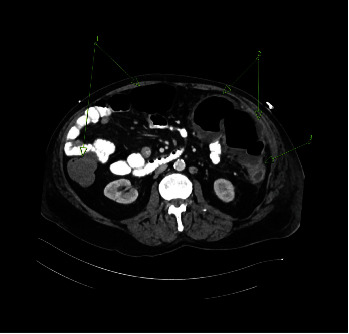

Inflammatory myofibroblastic tumor (IMT) is a rare mesenchymal tumors of unknown etiology composed of myofibroblastic cells admixed with inflammatory cells. Presented is a 72-year-old male hospitalized for severe abdominal pain and hematochezia with onset of associated symptoms of fever and sweats a few hours prior to abdominal pain. A computed tomography (CT) demonstrated left colonic thickening interpreted as partial obstruction, gross adhesions, and ischemia. At surgery, marked bowel ischemia from the distal transverse to proximal sigmoid colon was seen with extensive gross adhesions. Histopathology revealed a mesenteric mass chiefly composed of stellate-to-spindled myofibroblastic cells and fibrous adhesions, intermixed with lymphocytes, histiocytes, and plasma cells. The tumor was positive for desmin, smooth muscle actin, and keratin; tumor staging, grade, and postsurgical follow-up were not completed as the patient expired postoperatively. Illustrated is a rare pathologic mimic of ischemic colitis with fibrous adhesions, IMT. Thus, it should not be assumed that fibrous adhesions are always the etiology of obstruction when "adhesions" between sections of bowel are noted radiologically or surgically.

Abstract Image